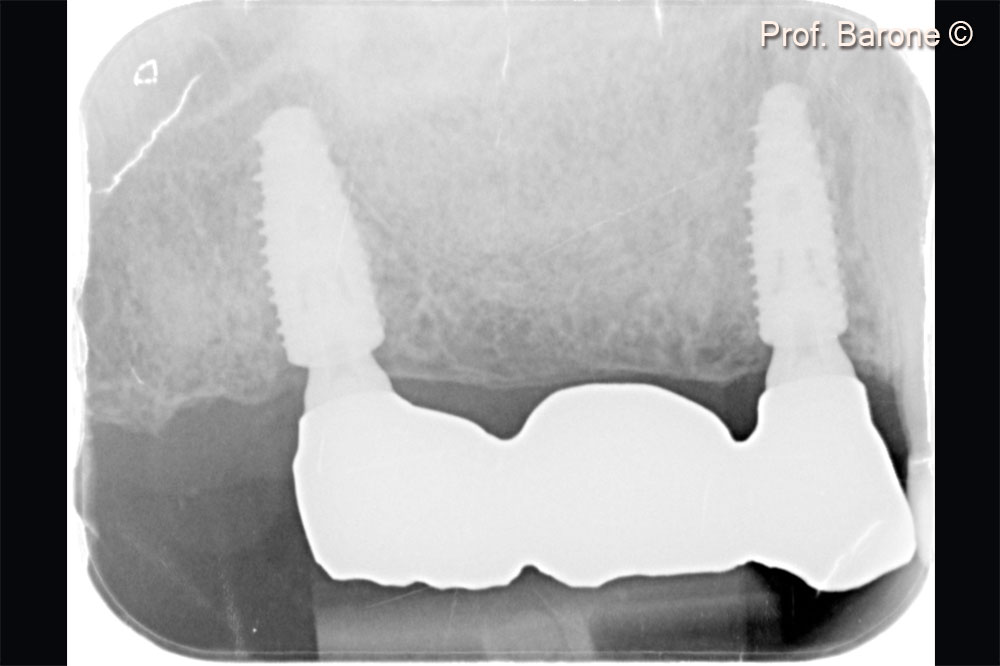

Periapical X-Ray 2 years after implant placement